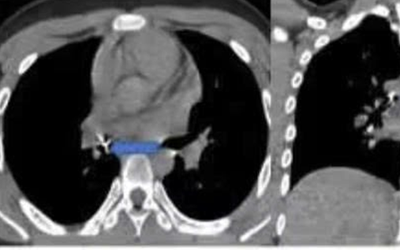

Trong lúc chơi và xem điện thoại, bé trai 13 tuổi vô tình hít phải thứ quen thuộc này khi đang ngậm trong miệng, khiến dị vật sắc nhọn xuyên sâu thành phế quản.